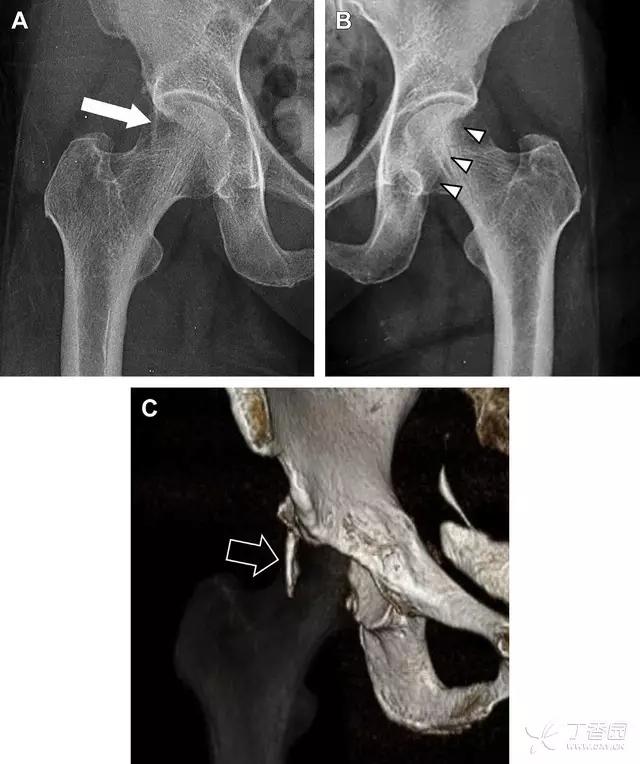

髋臼骨折最常见的类型是髋臼后壁骨折,几乎占髋关节骨折的 1/4,且常常合并髋关节后脱位。由于骨性结构重叠,可能肉眼看上去觉得非常轻微的骨折,事实却并非如此。髋臼后缘中断常常是髋臼后壁骨折的一个特征(图 2)。

图 2 为髋臼后壁骨折伴髋关节脱位患者。A 右侧髋关节 X 线片示股骨头后方可见一骨折线(箭头),髋臼后缘中断。B 左侧髋关节 X 片对照可见髋臼后缘连续(箭头)。C CT 三维重建图像示髋臼后壁缺损,可见旋转、移位的骨折块(箭头)